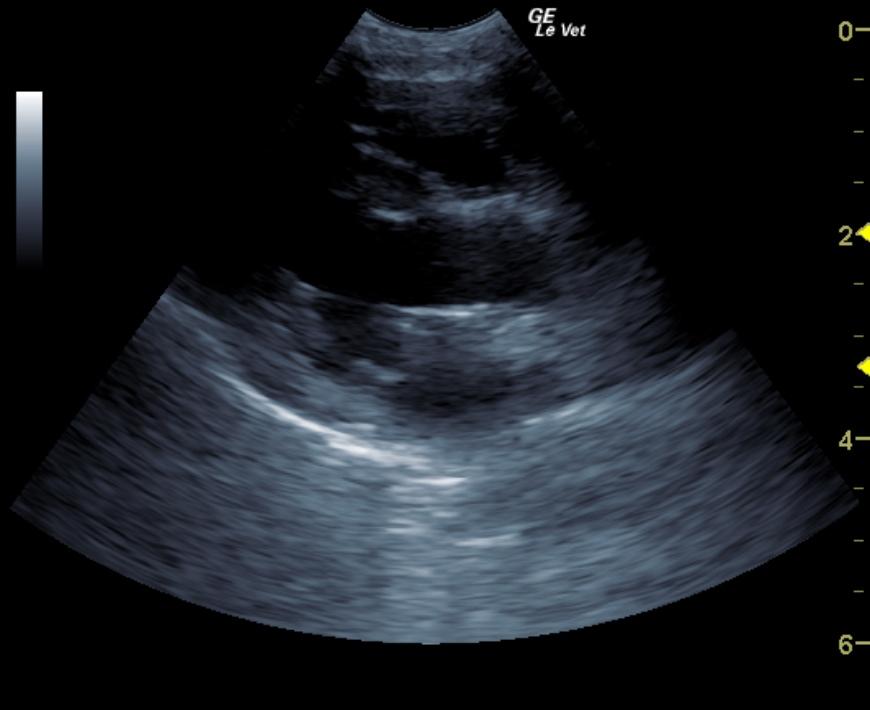

A 10 year old female spayed Maltese was presented for excessive urination. The only significant abnormality on physical examination was a grade II/VI systolic heart murmur. On urinalysis, an inappropriate SG and 2+ proteinuria was present. CBC was within normal limits, but blood chemistry showed elevated ALT activity and azotemia. T4 was 1.2.